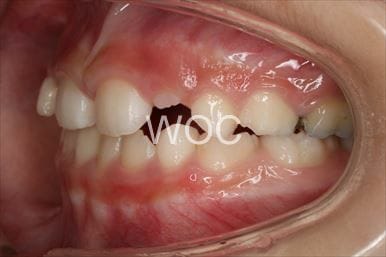

治療前1

-

治療前2

-

治療前3

- 年齢:32歳女性

- 主訴:前歯で噛めない

- 基本矯正料金:80万円

- 治療期間:1年11ヶ月

- 抜歯部位:上顎右側第一小臼歯、上顎左側第二小臼歯

-